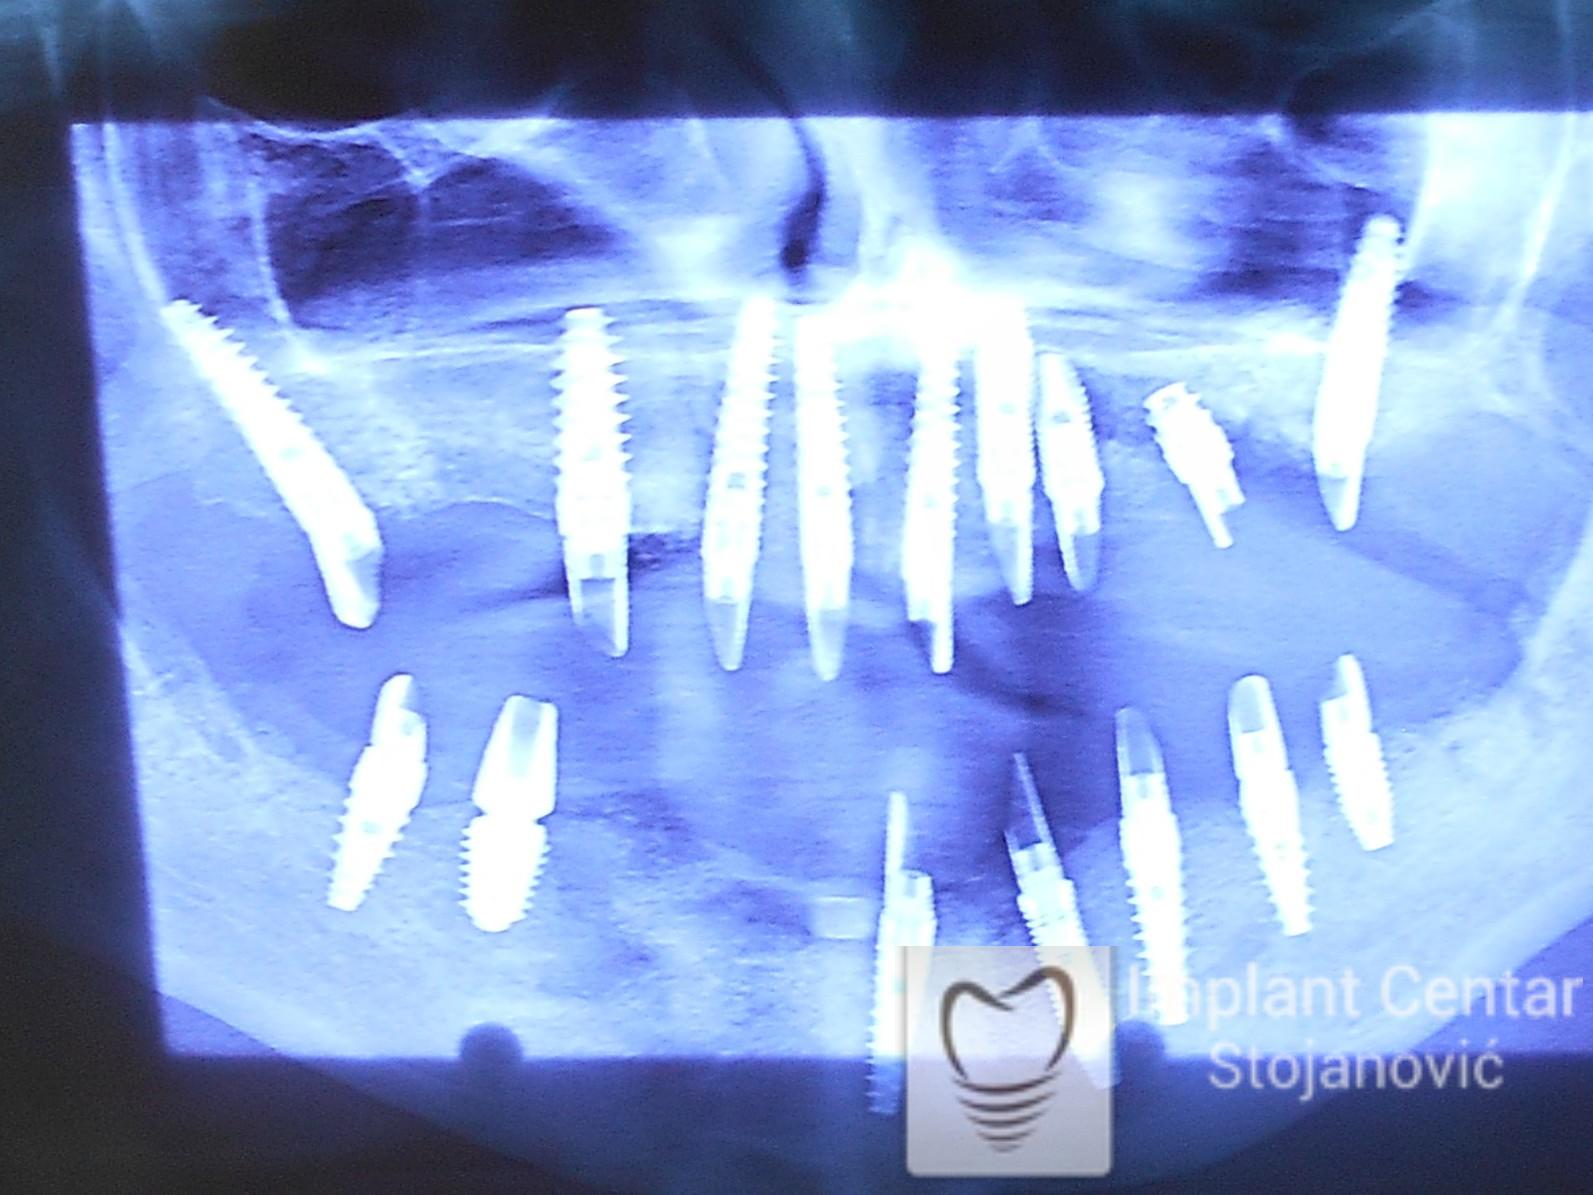

Zbog toga je plan terapije uključivao vađenje svih preostalih zuba i ugradnju implantata u gornjoj i donjoj vilici. U gornjoj vilici postavljena su i dva tuberopterigoidna implantata, kao zamena za sinus lift proceduru, što se može videti na ortopan snimku nurađenom odmah nakon ugradnje (slika 3).

Nakon vađenja zuba, ugrađeni su implantati. Na slici 3 prikazan je ortopan snimak sa ugrđenim implantatima. Tokom perioda osteointegracije, pacijent je bio zbrinut fiksnim privremenim krunicama na implantatima, koje su izrađene samo dva dana nakon hirurške intervencije.